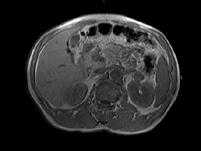

问题 男,52岁,下肢无力伴多饮多尿2?年余,实验室检查:低血钾,血醛固酮水平及24小时尿醛固酮定量超过正常值,MRI检查如图所示,应诊断为()

选项 A.左肾上腺囊肿 B.左肾上腺腺瘤 C.左肾上腺嗜铬细胞瘤 D.左肾上腺髓脂瘤 E.左肾上腺转移瘤

答案 B